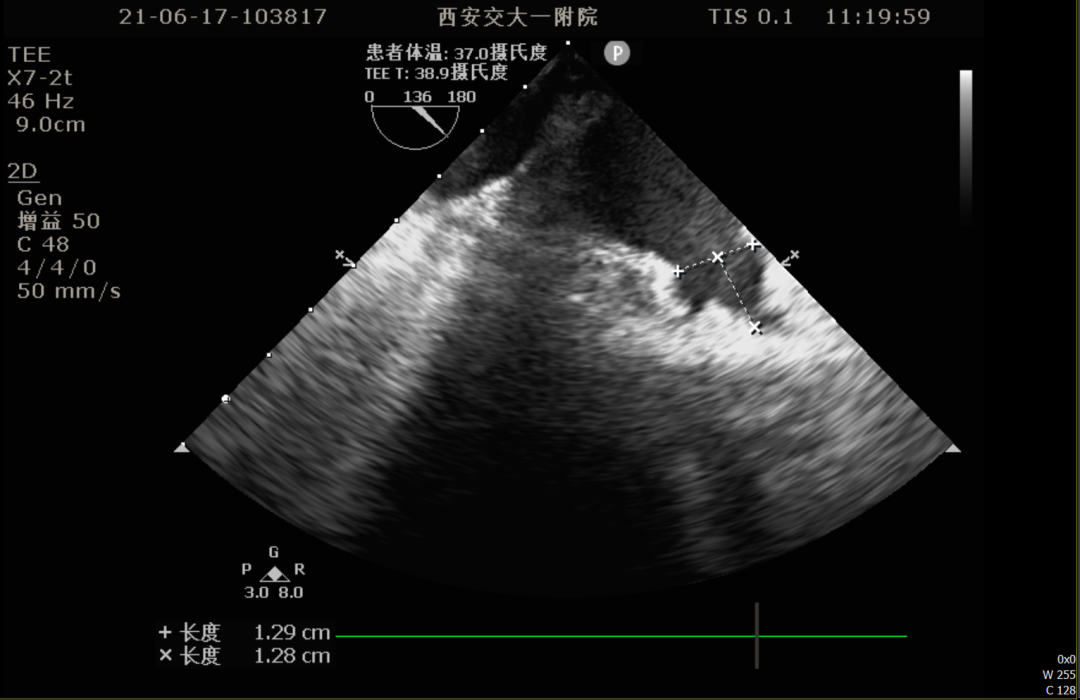

术前TEE评估

术前排除左心耳血栓,左心耳可能呈反鸡翅型,心耳偏小,梳状肌发达。

0°TEE

86°TEE

TEE测量左心耳数据:

TEE测量结果:

该患者左心耳开口较小,呈反鸡翅型,开口处即反折,同时内部梳状肌发达,且深度较浅,因此手术难度偏大,术前安排进一步CT评估以协助制定手术策略。